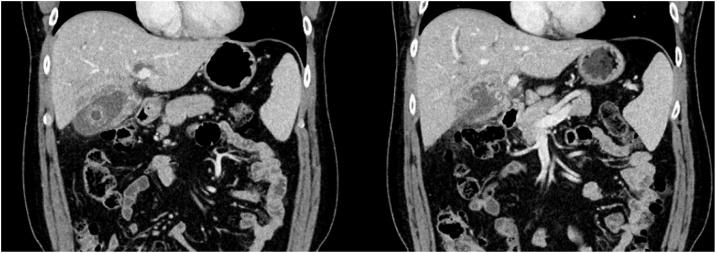

一名48岁男性因胆绞痛和体重减轻前来就诊,超声检查发现有胆结石。在随后的随访中,他出现了深度黄疸,肝功能紊乱,CT显示有胆囊肿块和胆管扩张。后续的磁共振胰胆管造影(MRCP)提示为XGC并伴有MS,但不能排除恶性病变。在为其黄疸进行经皮胆道引流时,术前细针穿刺抽吸细胞学检查(FNAC)显示为XGC,无恶性证据。鉴于腹腔镜检查时炎症严重且积脓张力高,他接受了开窗式胆囊次全切除术。最终的组织病理学诊断为急性胆囊炎。

我们的患者可能最初患有未被识别的急性胆囊炎,进而发展为伴有积脓和I型Mirizzi综合征的复杂肿块,最终导致类似胆囊癌的严重梗阻性黄疸。鉴于在这些严重炎症病例中进行腹腔镜胆囊全切除术很危险,开窗式胆囊次全切除术已被证明是一种比更具侵入性的手术策略更安全的替代方法,并成功应用于我们的患者。